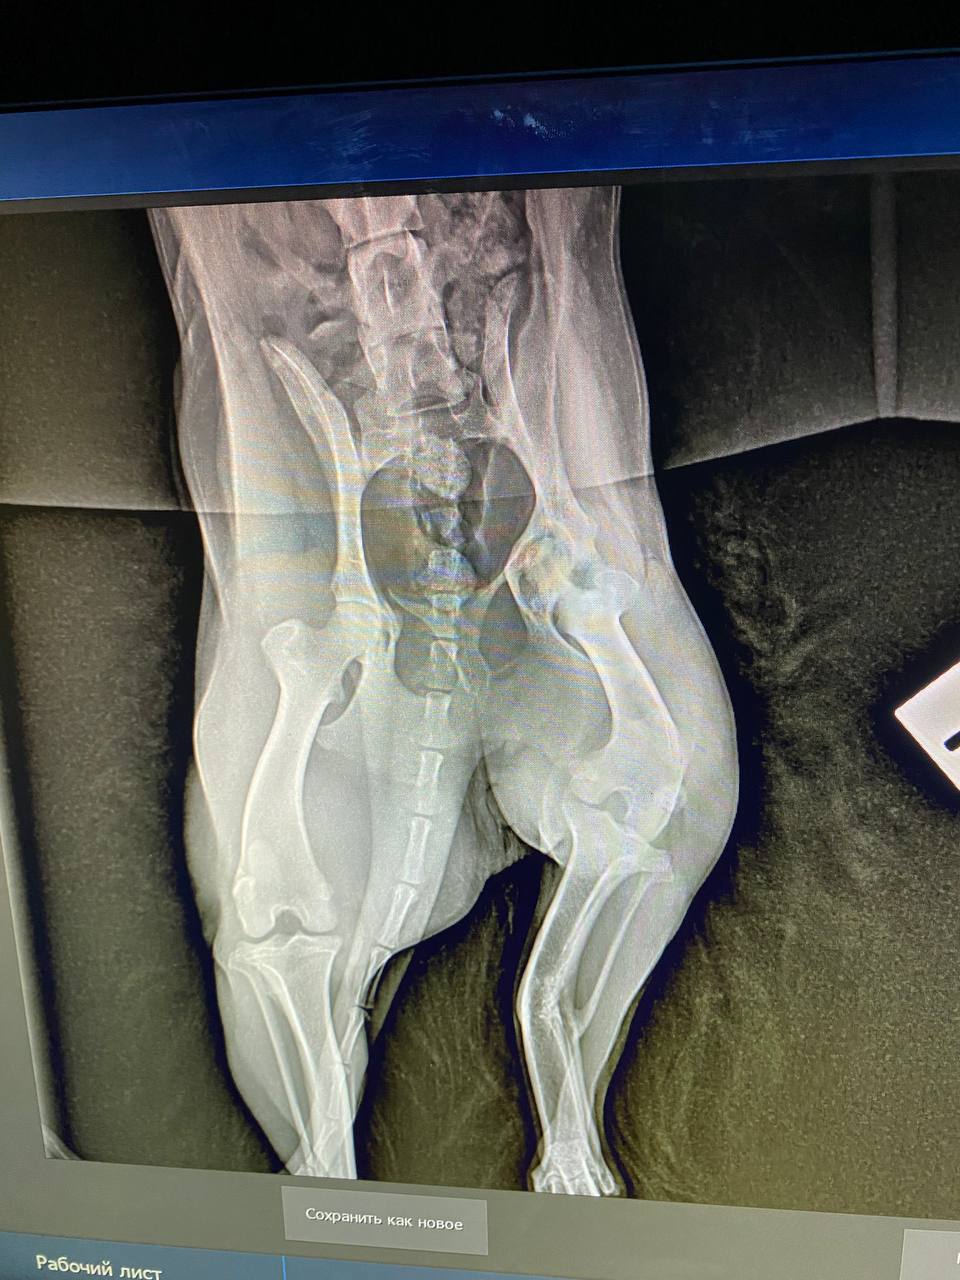

Сходили к ортопеду, у Люси перелом лапы в трех местах, уже сросшийся. Предлагают операцию в 2 этапа.

вот это перелом...она не под машину или какой транспорт попала, интересно. У нее получается в нижнем переломе верхняя часть кости срочлась с серединой нижнего обломка?

Похоже, что под машину. Когда ее нашли, видимо, свежий был перелом. Но пока волонтеры там мумили, хотя мы сразу согласились забрать, срослось все наперекосяк(Анастасия Нибелунг писал(а): ↑10 апр 2026, 20:33 вот это перелом...она не под машину или какой транспорт попала, интересно. У нее получается в нижнем переломе верхняя часть кости срочлась с серединой нижнего обломка?

Оксана ездила с Люсей ещё раз в Колпино на консультацию:

Возможно будет 3 этапа операций, поскольку у Люсьенки по КТ стало понятно , что еще повреждена голень, вывернута неестественно вправо.

Первый этап не меняется. Начинаем с таза, делают резекцию, если правильно запомнила. Реабилитация 2-4 месяца. Смотрим по итогу как встанет лапа, возможно, нам повезет и больше операций не потребуется. Стоимость первого этапа 30 тыс.

Если после первой операции и реабилитации понимаем, что лапа не встала до конца в естественное положение, следующий этап колено. Опять реабилитация, смотрим итог. И если снова лапа не выравнивается, дальше чиним голень. Но мы держим кулачки и надеемся, что обойдемся одной операцией, максимум двумя

Люсю сегодня прооперировали, сделали резекцию тазобедренного сустава.

Через 2 недели снимать швы, через месяц надо показаться врачу, как идет реабилитация и надо ли планировать следующую операцию.